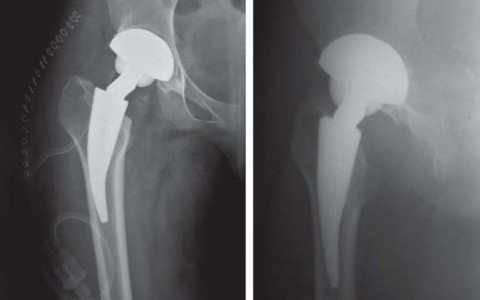

تُعد الأشعة السينية (X-rays) الأداة التشخيصية الأساسية لتصوير مفصل الفخذ. يُطلب عادة:

* صورة شعاعية أمامية خلفية (AP) للحوض مع كلا مفصلي الفخذ: هذه الصورة تسمح بتقييم شامل لكلا المفصلين، وتحديد مركز رأس الفخذ، وطول الساق، والإزاحة (offset)، ومستوى قطع عنق الفخذ المحتمل، وحجم الجذع.

* صورة شعاعية جانبية للمفصل المصاب مع تكبير 15%: لتوفير رؤية إضافية لهيكل المفصل وتخطيط الزرع.

التخطيط قبل الجراحة

يُعد التخطيط الدقيق قبل الجراحة أمرًا بالغ الأهمية لنجاح جراحة METHA قصير الجذع. يتضمن ذلك استخدام قوالب خاصة على الأشعة السينية لـ:

* تحديد حجم الزرعة: اختيار الحجم المناسب للجذع والمكون الحُقي.

* تخطيط قطع عنق الفخذ: يجب أن يكون القطع بزاوية 50 درجة بالنسبة للمحور الطولي لعظم الفخذ، مع الحفاظ على 5-10 ملم من القشرة الجانبية لعنق الفخذ.

* استعادة ميكانيكا المفصل: ضمان استعادة مركز رأس الفخذ، وطول الساق، والإزاحة إلى الوضع الفسيولوجي الطبيعي.

* تحديد زاوية عنق الفخذ: تُقاس زاوية عنق الفخذ في الجانب غير المصاب إن أمكن، لمساعدة الجراح في اختيار محول العنق المناسب أثناء الجراحة.

تساعد هذه الخطوات الدقيقة في ضمان اختيار الزرعة المناسبة وتحديد موضعها الأمثل، مما يقلل من مخاطر المضاعفات ويحسن النتائج الوظيفية للمريض. يتمتع الأستاذ الدكتور محمد هطيف في صنعاء بخبرة واسعة في التخطيط الدقيق وتنفيذ هذه الجراحات المعقدة، مستخدمًا أحدث التقنيات لضمان أفضل النتائج لمرضاه.